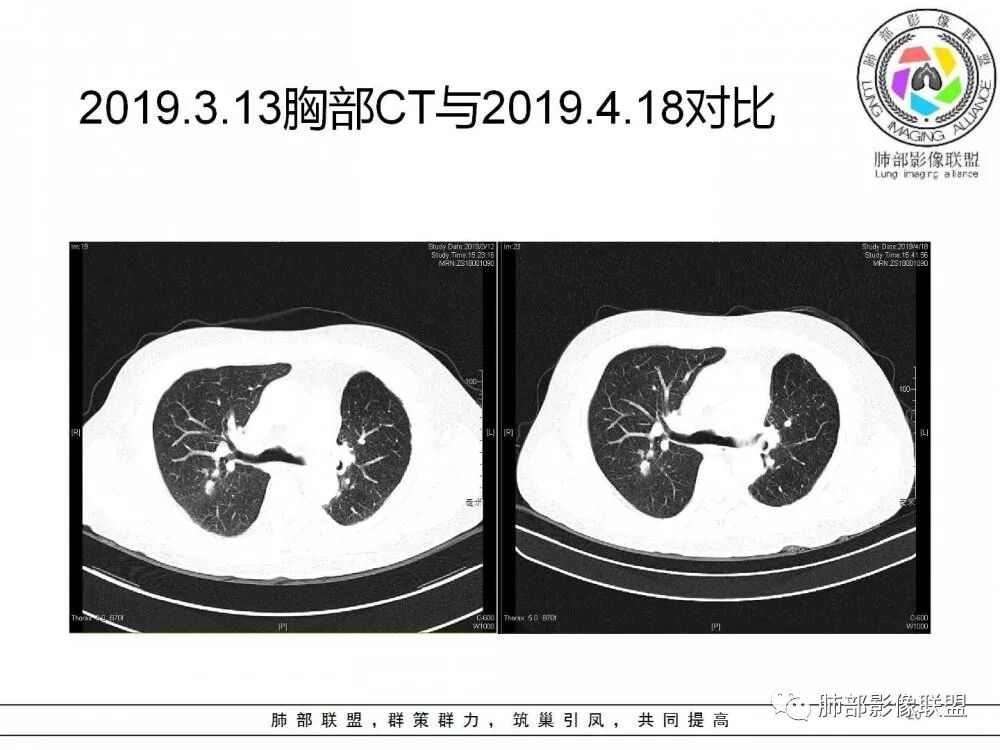

肺部病灶从2月份就开始有了,应该最早说是1月7号就有了,到3月13号稍微增大一点,到后面几乎就没变化了,到5月份好像稍微大一些,炎性肯定是炎性,就是这个炎性是到底什么病变呢?其实本没变化,它特点一个是在叶裂上,跟血管关系密切,但是病灶边缘稍收缩,病灶这么没有太大变化,我还是支持炎性病变。

确实当时病人来了考虑转移可能,就测了基因,上了靶向药,两月变化不大

因为这个长轴似乎跟支气管走行一致的,其实治疗效果不是很理想,我先把性质定为炎性。因为这个病灶它沿着血管支气管走行的方向,大家都考虑隐球菌,这么久病灶无明显变化,它跟血管束关系很密切。我犹豫就在此,到底是IgG4还是隐球,大方向是炎性,不符合的就是也在激素治疗。

19年3月份才吃靶向药